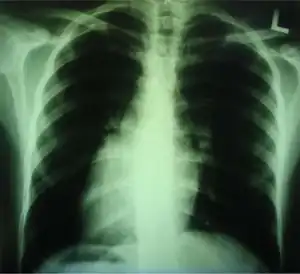

Dextrocardia (from Latin dextro, meaning "right hand side," and Greek kardia, meaning "heart") is a rare congenital condition in which the apex of the heart is located on the right side of the body, rather than the more typical placement towards the left.[1][2]

Dextrocardia situs inversus refers to the heart being a mirror image situated on the right side. For all visceral organs to be mirrored, the correct term is dextrocardia situs inversus totalis.[5][6]

Medical diagnosis of the two forms of congenital dextrocardia can be made by ECG[3] or imaging.